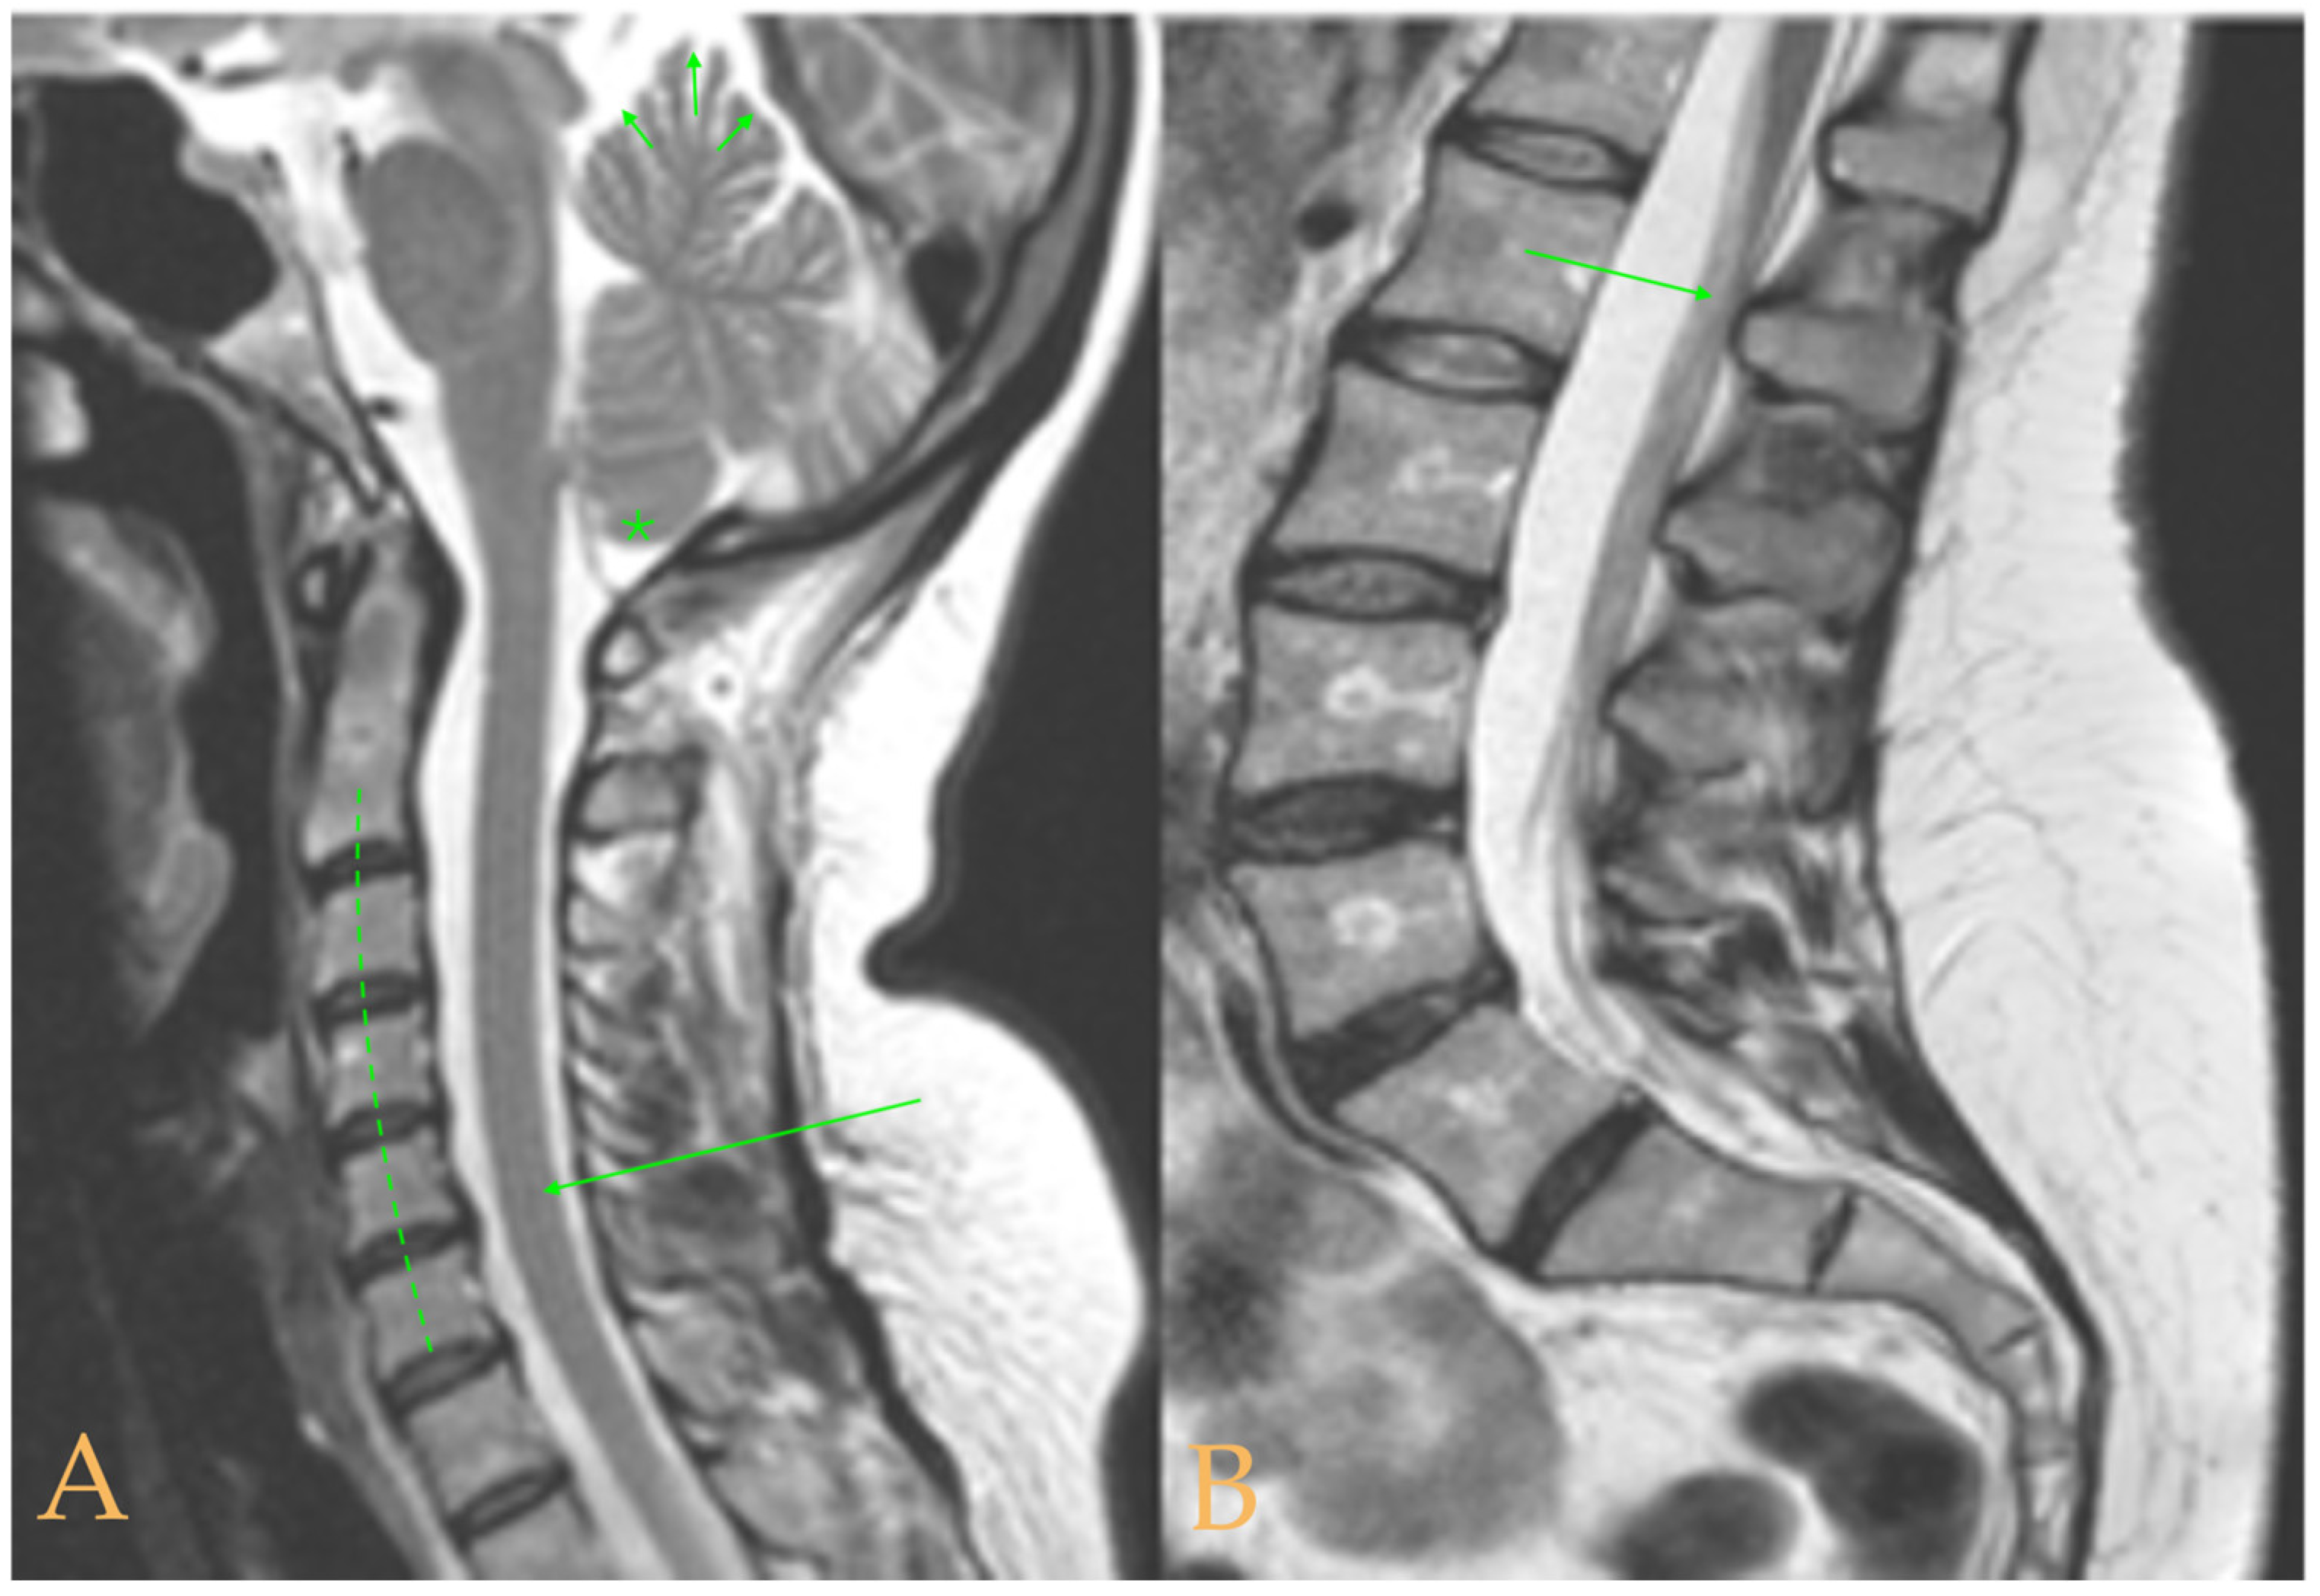

The MRI showed descent of the cerebellar tonsils, 13 mm pineal cyst, and multiple disc protrusions in T4-T8 and T9-T10, with herniation T5-T6. Straightening of the thoracic and lumbar spine. Low conus medullaris at the upper third level of the L2 vertebra (Figure 7). The full-spine X-rays showed a mild double-curved thoracic and lumbar scoliosis (<10° Cobb), and lower extremity dysmetria with shortening of the left lower extremity estimated to be 3 mm at the level of the acetabular roofs and 7 mm at the level of the iliac crests. Dextroconvex lumbar scoliosis was estimated to be 2°, and levoconvex cervicothoracic scoliosis was estimated to be 10° (both total, including all vertebrae). The estimated lateral curves, including all vertebral bodies in each region, were cervical lordosis 25°, thoracic kyphosis 34°, and lumbar lordosis 53°.

Figure 7. Imaging of patient 7. A: Descent of the cerebellar tonsils (star); B: straightening of the cervical spine (interrupted line) with image suggestive of medullar ischemia (arrow); and C: straightening of the upper part of the lumbar spine (interrupted line) and conus medullaris at the level of the upper third of L2 (arrow).